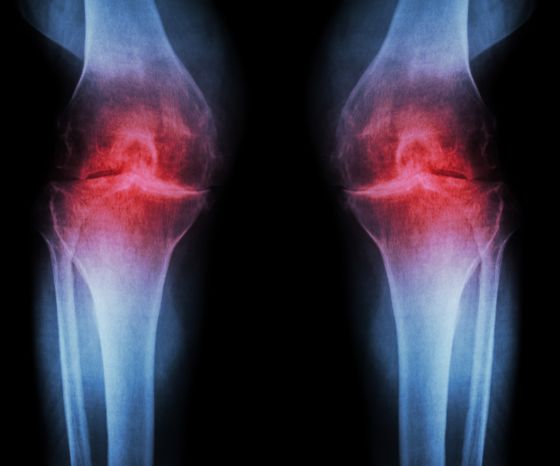

السمة الكلاسيكية للالتهاب المفصلي العظمي للركبة هي التغيرات النسيجية في نوعية وسمك غضروف المفصل. يؤدي انخفاض في غضروف المفصل إلى تضخم العظم تحت الغضروف وتكوين نابتة عظمية عند حواف أسطح المفاصل. نتيجة أخرى هي الالتهاب المزمن في النسيج الزليلي. تؤدي كل هذه التغييرات إلى عدم انتظام أسطح المفاصل وتضخم العظام واحتمال زيادة سماكة كبسولة المفصل وفي النهاية حدوث استسقاء. يظهر الانخفاض الناتج في مساحة المفصل في الصور الشعاعية، ولهذا السبب نتحدث أيضاً عن "الفصال العظمي الإشعاعي".

نظام التصنيف الأكثر استخدامًا لالتهاب المفاصل الإشعاعي هو مقياس كيلغرين ولورانس (كون وآخرون. 2016):

- الدرجة 0: لا توجد أي سمات إشعاعية للالتهاب الرئوي المزمن

- الدرجة 1: تضييق مشكوك فيه في مساحة المفصل واحتمال وجود شفة نابتة عظمية

- الدرجة 2: وجود نابتات عظمية محددة واحتمال وجود تضيق في مساحة المفصل على الصورة الشعاعية الأمامية الخلفية الحاملة للوزن

- الدرجة 3: نابتات عظمية متعددة، وتضيق واضح في مساحة المفصل، وتصلب، وتشوه عظمي محتمل

- الدرجة 4: نابتات عظمية كبيرة وضيق ملحوظ في مساحة المفصل وتصلب شديد وتشوه عظمي واضح